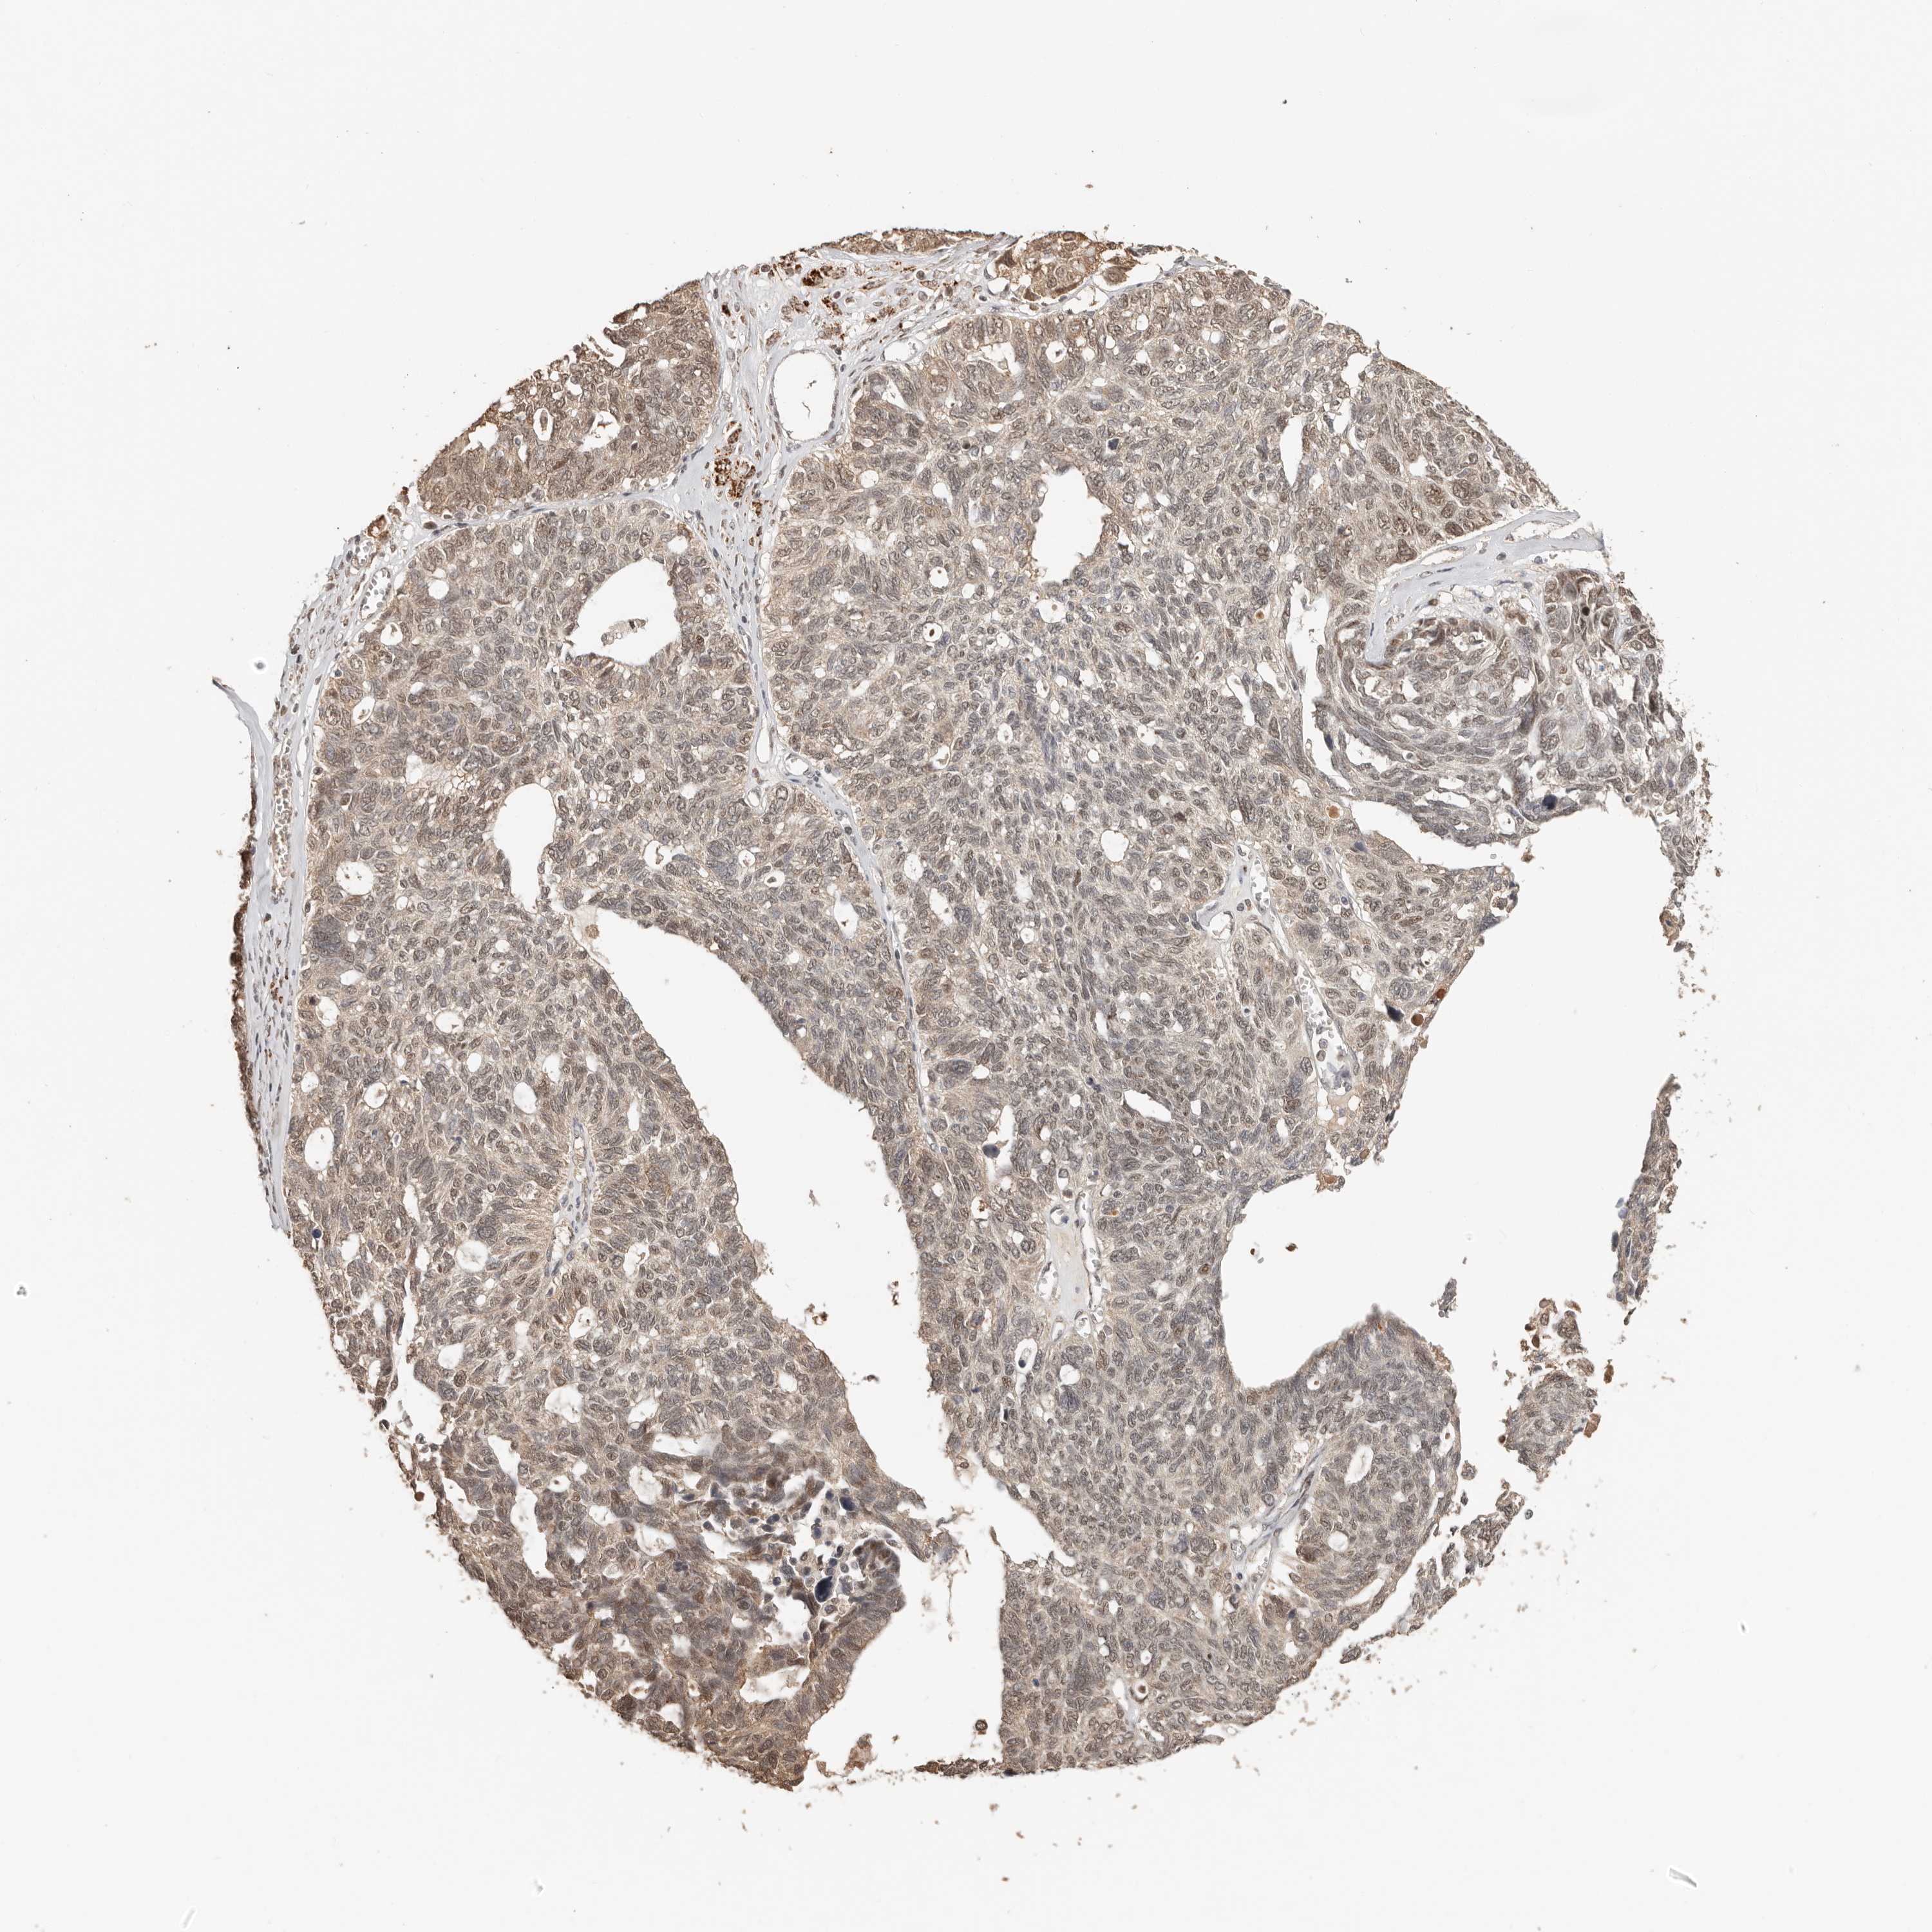

OVARIAN CANCER - Protein expressioni

A mouse-over function shows sample information and annotation data. Click on an image to view it in a full screen mode. Samples can be filtered based on level of antibody staining by selecting one or several of the following categories: high, medium, low and not detected. The assay and annotation is described here.

Note that samples used for immunohistochemistry by the Human Protein Atlas do not correspond to samples in the TCGA dataset.

Antibody stainingi

Antibody staining in the annotated cell types in the current human tissue is reported as not detected, low, medium, or high, based on conventional immunohistochemistry profiling in selected tissues. This score is based on the combination of the staining intensity and fraction of stained cells.

Each image is clickable and will lead to virtual microscopy that enables deeper exploration of all samples and also displays staining intensity scores, fraction scores and subcellular localization as well as patient and tissue information for each sample.

Antibody HPA028703

High

Medium

Intensity

Strong

Quantity

>75%

Location

Nuclear

Cytoplasmic/membranous

Cytoplasmic/membranous,nuclear

Carcinoma, endometroid

Cystadenocarcinoma, mucinous, NOS

Carcinoma, NOS

Cystadenocarcinoma, serous, NOS